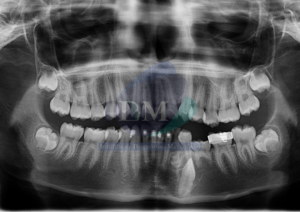

Caso 285 – IDM – CANINO IMPACTADO EN POSICIÓN ECTÓPICA IDM

Paciente femenina de 32 años de edad acude al instituto de Diagnóstico maxilofacial – IDM (surco) para evaluación imagenológica de terceros molares. En la radiografía panorámica